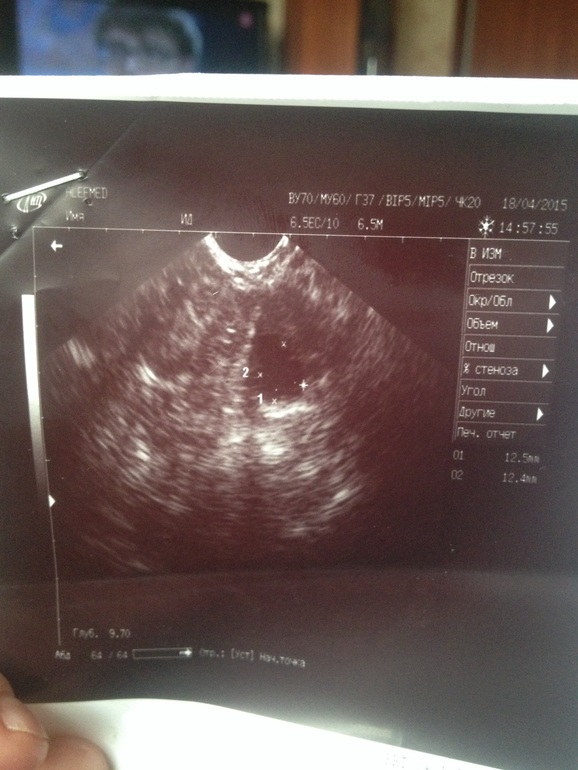

первое от 15.04, 13 дц. доминантный фолликул 17,7, эндометрий 7,7. сказала, что О ближе к выходным. Тест на О 16,04 яркая полоска, 17,04 слабая. вчера (17,04) стреляющие боли в Я ( у меня он один, только правый). Сегодня пошла на УЗИ( второе фото). Это ппц......Житкость она не увидела, увидела, фолликулы 6 и 9 мм, после того как я сказала, что был 17, она нашла фолликул 12 мм. Сказала, что наверно он уменьшился и О не было. Кроме того сказала, что у меня двурогая матка)))))))))))) А после моих слов, что это не так( я рожавшая и пережившая полосную операцию) она заявила, что видит это и лучше знает. жидкости тоже не видит( плиз..... посмотрите пожалуйста фото) потому что я на втором( сегодняшнем) снимке вижу ЖТ!!! Или я дура уже просто сходящая с ума! Еще нашла спаечный процесс, которого никто раньше не видел ( за последние 3 месяца сделала 6 УЗИ) Кстати, в заключении ни про матку, ни про эндометрий не написано. Это УЗИстка некомпетентная или я уже умом тронулась!

В итоге переделала УЗИ, 20 дц. О была, все в порядке! ЖТ 15 мм, эндометрий 13 мм)))) УЗИстка показала ЖТ на экране, как раз на том месте где предыдущая увидела Фоликул 12) ура)

Спасибо) вы знаете, не хочу обнадеживать, но вообще больше на жт похоже. Но это сугубно мнение профана, я не врач. Если очень интересно, то сходите еще на узи в другое место.

Так я тоже смотрела в нете как выглядит сдувшийся фолликул и ЖТ, то похоже на ЖТ. В понедельник еще обязательно схожу) ну что хотеть от специалиста, если она у меня матку двурогую увидела! Еще и спорила со мной! Спасибо вам огромное за поддержку, я уже успокоилась, а то такая гадость в голову приходила!

Сейчас уже сложно определить по фотографии, разве что вы вспомните, когда вас смотрели на узи, было ли свечение вокруг, если да, то точно жт. А еще если внутри видели бугорок, как язычок такой, тоже. Ну а самое простое, померяйте завтра утром базальную температуру(если не в курсе, то ректально, 5 мин, примерно в 7-00 утра, не позже)если будет 37 то точно была овуляция